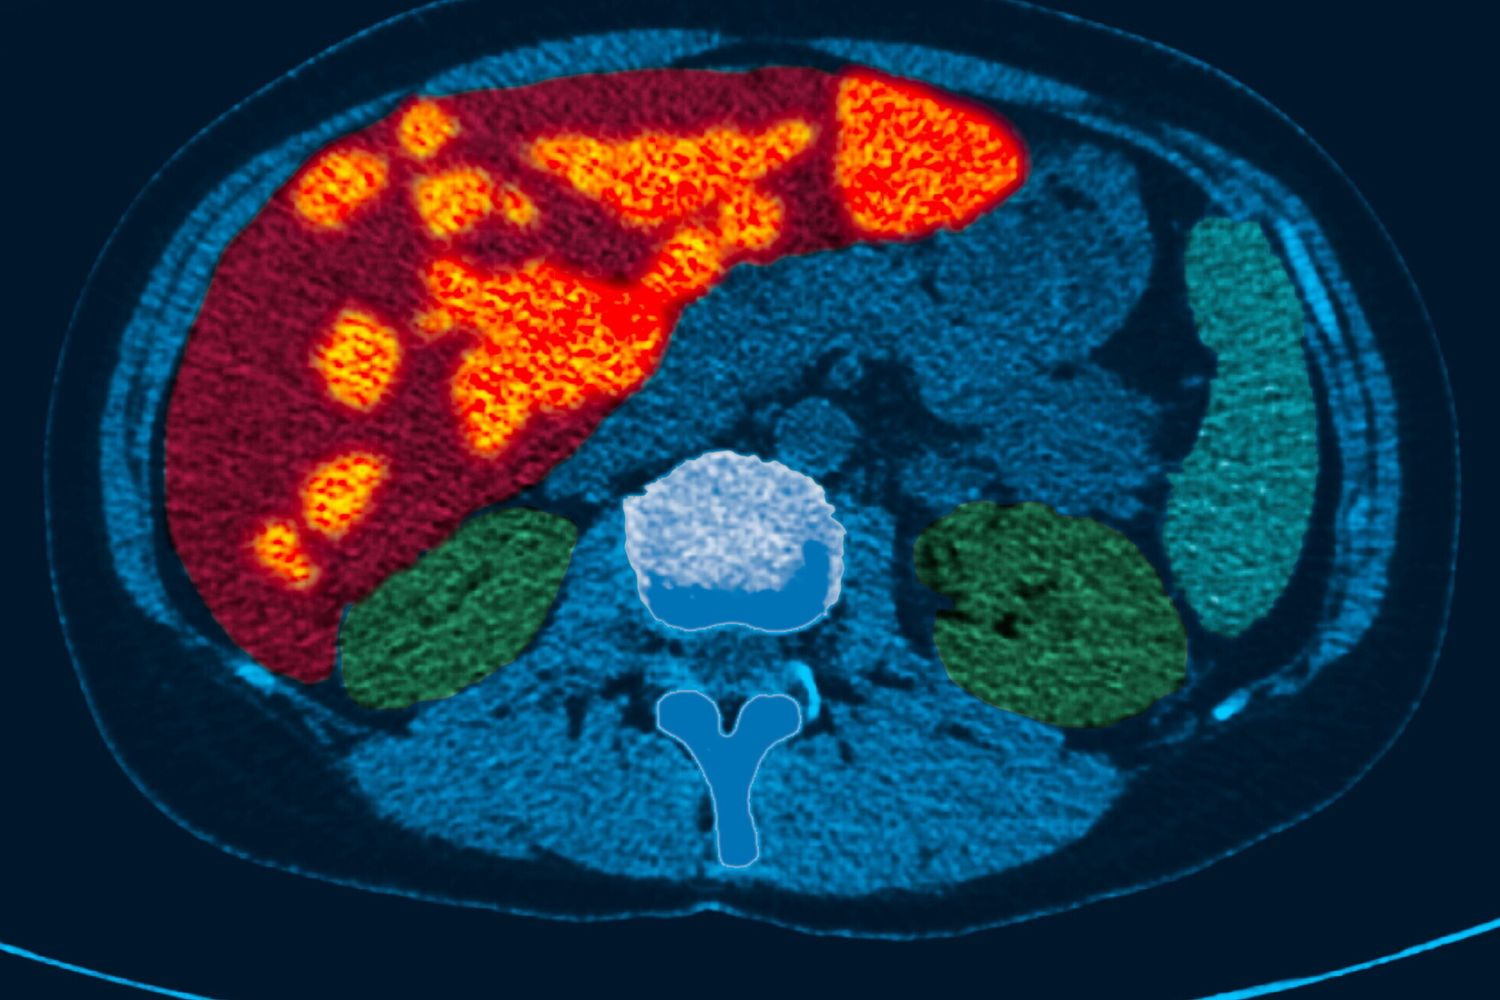

AGI - Il lawsone, pigmento attivo dell’henné Lawsonia inermis, potrebbe fungere come potenziale inibitore dell’attivazione delle cellule staminali epatiche, con implicazioni nella cura della fibrosi epatica. Lo rivela uno studio guidato da Tsutomu Matsubara e Atsuko Daikoku, dell’Università Metropolitana di Osaka. I risultati, riportati su Biomedicine & Pharmacotherapy, mostrano una riduzione dei marcatori di fibrosi e un possibile ri-orientamento delle cellule staminali verso uno stato meno fibrotico. L’approccio promette nuove vie per controllare o invertire la fibrosi, offrendo potenziali opportunità terapeutiche per una malattia con pochi trattamenti efficaci.

L’obiettivo dello studio è quello di individuare composti naturali in grado di modulare l’attivazione delle cellule stellate epatiche e di ridurre la fibrosi, offrendo una nuova strategia terapeutica per patologie epatiche croniche. Secondo i risultati, lawsone riduce marcatori di fibrosi epatica in modelli animali, suggerendo un effetto antifibrotico. L’approccio potrebbe guidare lo sviluppo di una classe di farmaci mirati alle cellule staminali epatiche attivate.